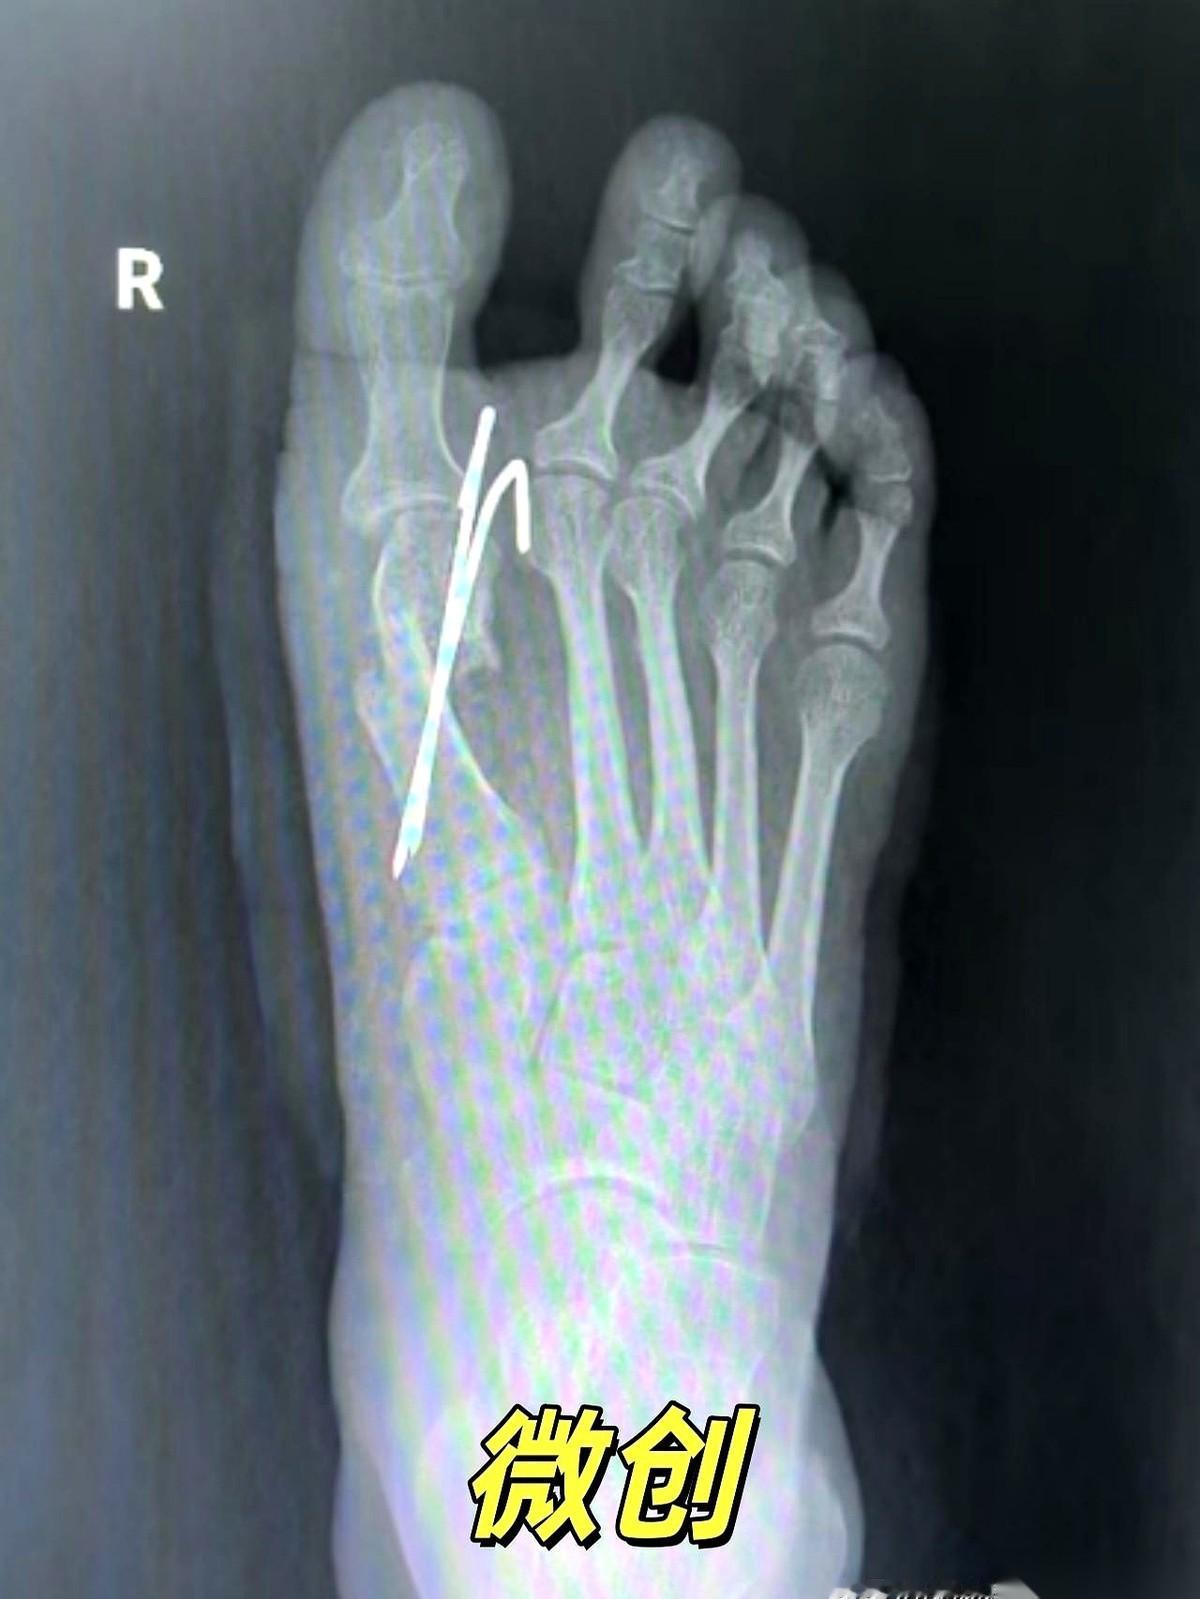

我跟你说,最狠的营销,就是把一个明明需要“伤筋动骨一百天”的事儿,包装成“随做随走”的下午茶。 拇外翻手术就是个典型的例子。 广告里,美女穿着高跟鞋,优雅地走出诊所,好像只是去修了个指甲。 但现实呢?现实是骨头被截断了,是真刀真枪地在你脚上动了刀子。 然后有人信了,真的去了。术后疼得龇牙咧嘴,脚肿得跟个馒头似的,跑去问医生。 医生云淡风轻一句:“挺好的,正常恢复。” 正常个鬼啊。 骨头断了,你拿什么固定?就靠外面绑个绷带? 这就好比房子的大梁歪了,你不用钢筋水泥去加固,反而在墙上贴了个“请勿靠近”的条子,指望它自己长结实? 做梦呢。 “不打钉”听起来好像多高级,多微创。 说白了,很多时候就是省事儿,但风险全留给了你。 骨头长歪了,畸形复发了,甚至得二次手术再遭一遍罪,这些广告里会说吗? 所以啊,别再被那些“不打钉、随做随走”的漂亮话给忽悠了。 下次你再咨询,就直接问那个最根本的问题: “医生,我这截断的骨头,您打算怎么让它稳稳当当地长好?” 看他怎么回答。 身体是自己的,不是试验田。任何手术,都得尊重最基本的生理规律。 捷径的尽头,往往是更远的路。